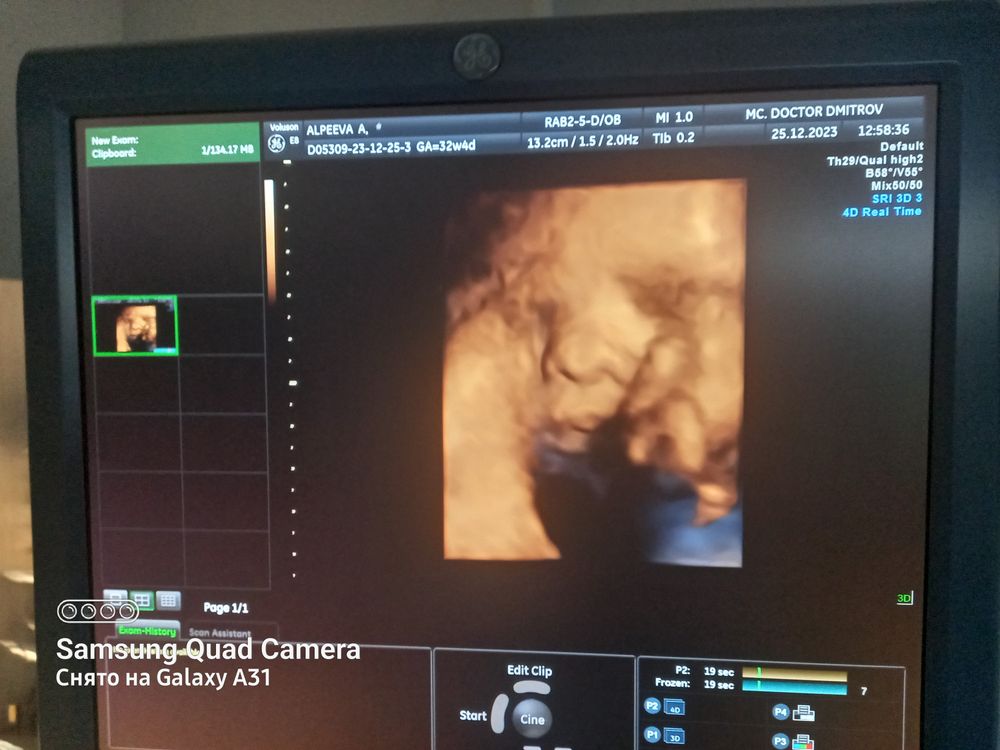

СкринингДевочки сегодня была на третьем скрининге, 32,4 нед. По узи опережает 33.2. Все ок, буквально за 2 дня сильно стало ломить промежность, прям тянет. На узи выяснилось, что из поперечного малыш перевернулся в головное буквально с той недели. Вес 2200 гр, кровотоки и т п в норме. Но первый раз такое, с волосами малышок) Первый два сына рождались без шевелюры, как бы были волосики, но прям приглаженные коротенькие. Тут узист как показала на мониторе, там такой причесон торчит🤭, замерила волосы 1.5 см. У кого так было, с какой прической в итоге рождались малыши? Это еще они подрастут волосики? Интересно, от чего такой интенсивный рост прически внутри мамы зависит, что я такого ем😅. Сделали фото личика на память)

Сладкоежка

Нам с мужем на третьем скрининге тоже показали волосики малыша, так они так хорошо видны, прямо торчат, я даже удивилась, я думала, что на узи такое не видно, и в 37 недель я ходила на фетометрию, тоже узист сказала, что отрастил волосики, и ещё интересно было наблюдать, как малыш дышит, так это хорошо видно было по его животику.

Сладкоежка, да, я сама удивленна, там прям наискосок торчит такой ирокез, вот сижу гадаю это какой же родится))) для меня очень необычно)